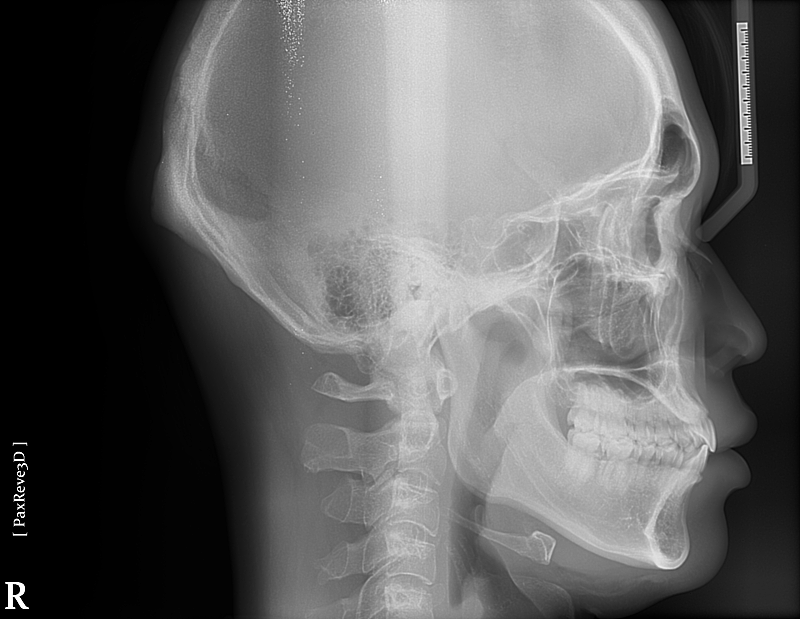

윗니가 앞으로 나오는 정도는 사람마다 다릅니다. 지금 사진상으로 보아 윗니가 앞으로 나온 양이 조금 적어 보이나

정상 범위입니다. 다만 오른쪽 작은 앞니(측절치)는 아랫니가 앞으로 나온 반대교합 입니다.